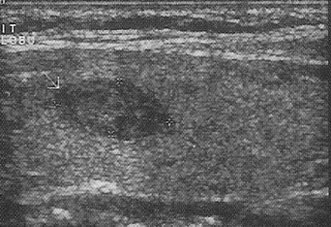

Ultrasonda tiroit kanser riski bulguları: Çapı 2.5-3cm'den büyük olan katı (Şekil 4) ya da karışık nodüller, çapı 4cm'den büyük kistik nodüller, kenarları düzensiz (Şekil 5) ve/veya içinde küçük kireçlenme odakları bulunan nodüller (Şekil 6), içinde ve etrafında kan akımı artmış olan nodüller ve izlemler sırasında büyüyen nodüller riskli nodüllerdir. Bunlardan bir kaçının beraber bulunması riski arttırır.

Fazla çalışan bir nodül (toksik nodül) varlığına da nodül ve çevresinde kan akımı artmış olabilir. Diğer yandan tiroitte yaygın olarak kan akımının fazla olduğunun saptanması, Graves hastalığı ya da Hashimoto hastalığı için bir gösterge olabilir (Şekil 7).

Şekil 4 ![]() | Şekil 5 ![]() | Şekil 6 ![]() | Şekil 7 ![]() |